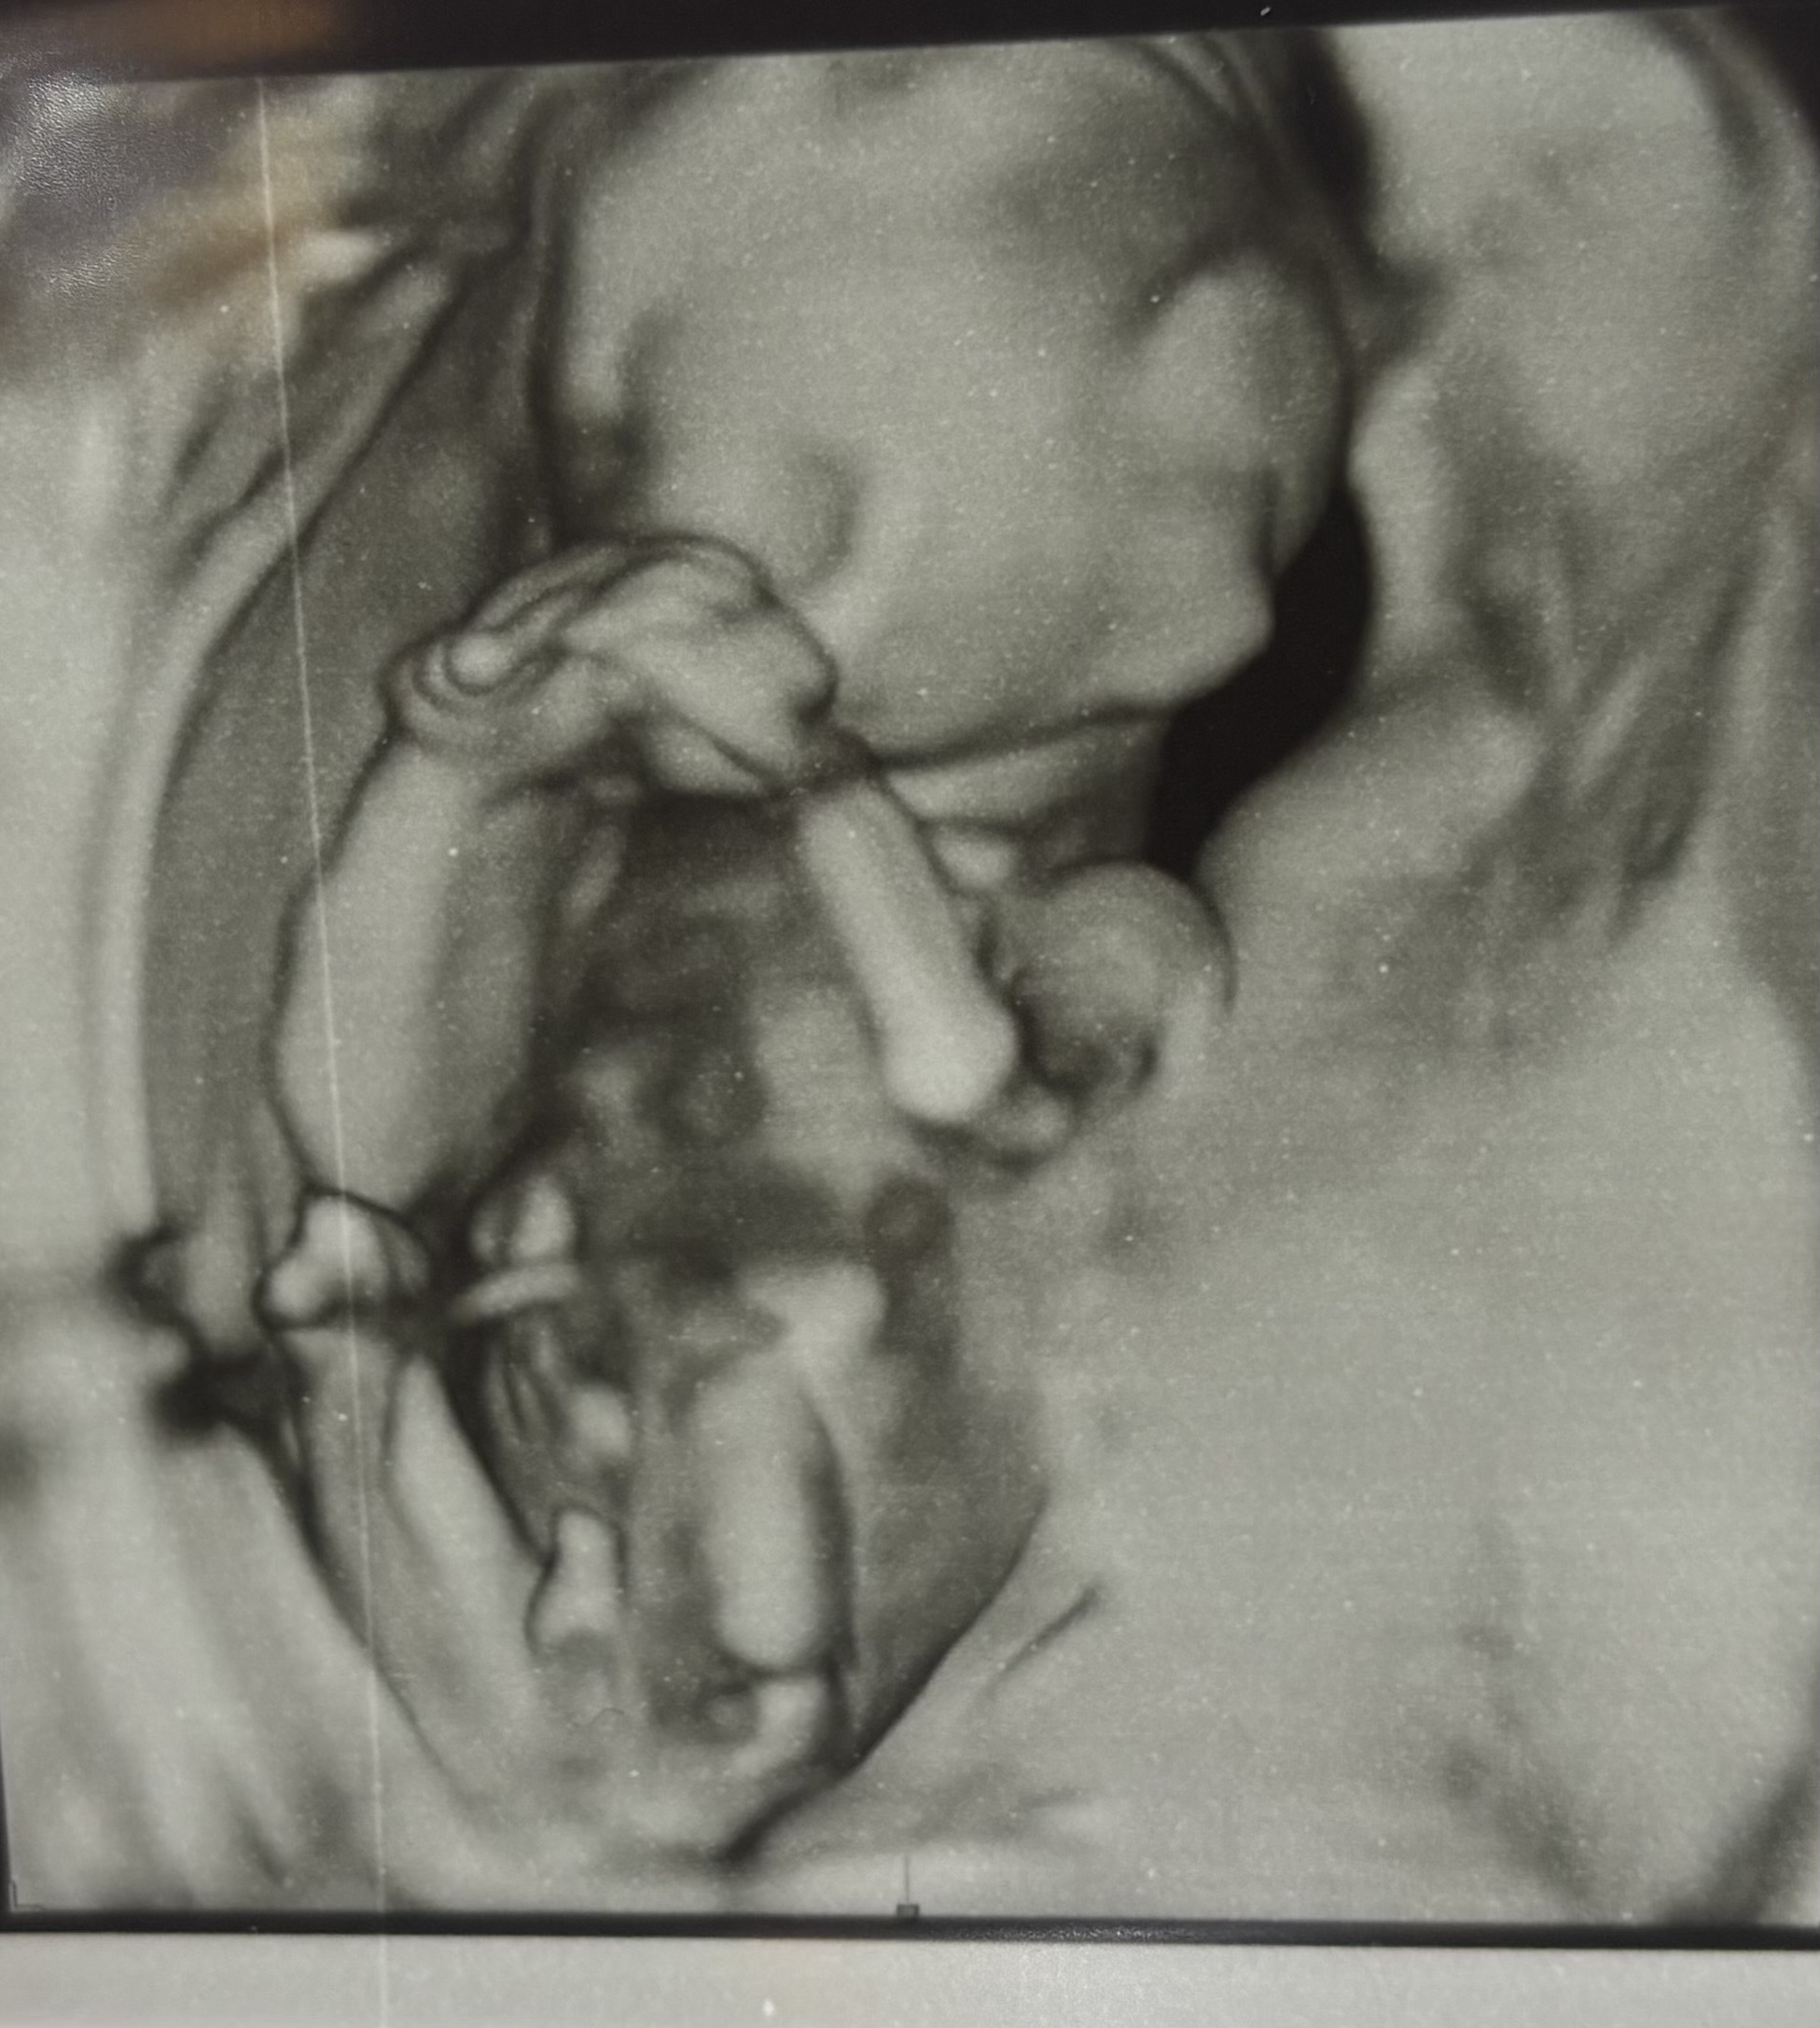

๋ช์ฃผ์ ๊ฐ์์ด์..? 14์ฃผ 5์ผ์ฐจ๋ ์ฑ๋ณ ๋ณด์ผ๊น์..?

์ ๋ ๋๋์ด ์ฑ๋ณ ๋ณด๊ณ ์์ด์~! ์ฒ์์ผ๋ก ์ฌ๋ ค๋ด ๋๋ค ใ ใ ์ ์๋์ด ๋ณด์๋๋ ๋ง ์ํด๋๋ ค๋ ๋๊ฒ ๋ค์ ํ์๋... ๋๋์ด ์ฑ๋ณ ์๊ฒ๋ผ์ ์์ด ๋๋ฌด ์์ํ๋ค์ ๊ฑด๊ฐํ๋ง ์๋ผ์ฃผ๋ ด~๐ฅฐ

ใ ใ ใ ๊ทผ์ํ๊ฒ ํฑ ๊ดด๊ณ ์๋ ๋ชจ์ต์ด ๋ ์๊ฐ์ด์์ ใ ใ ์๋ค๋ง ์ถํ๋๋ฆฝ๋๋ค โบ๏ธ

๊ฐ์ฌํด์ฏใ ใ ใ ๋จํธ์ด ์๊ทผํ ์์ฃผํ๋ ํฌ์ฆ๋ผ ๋ ์๊ธฐ๋๋ผ๊ณ ์